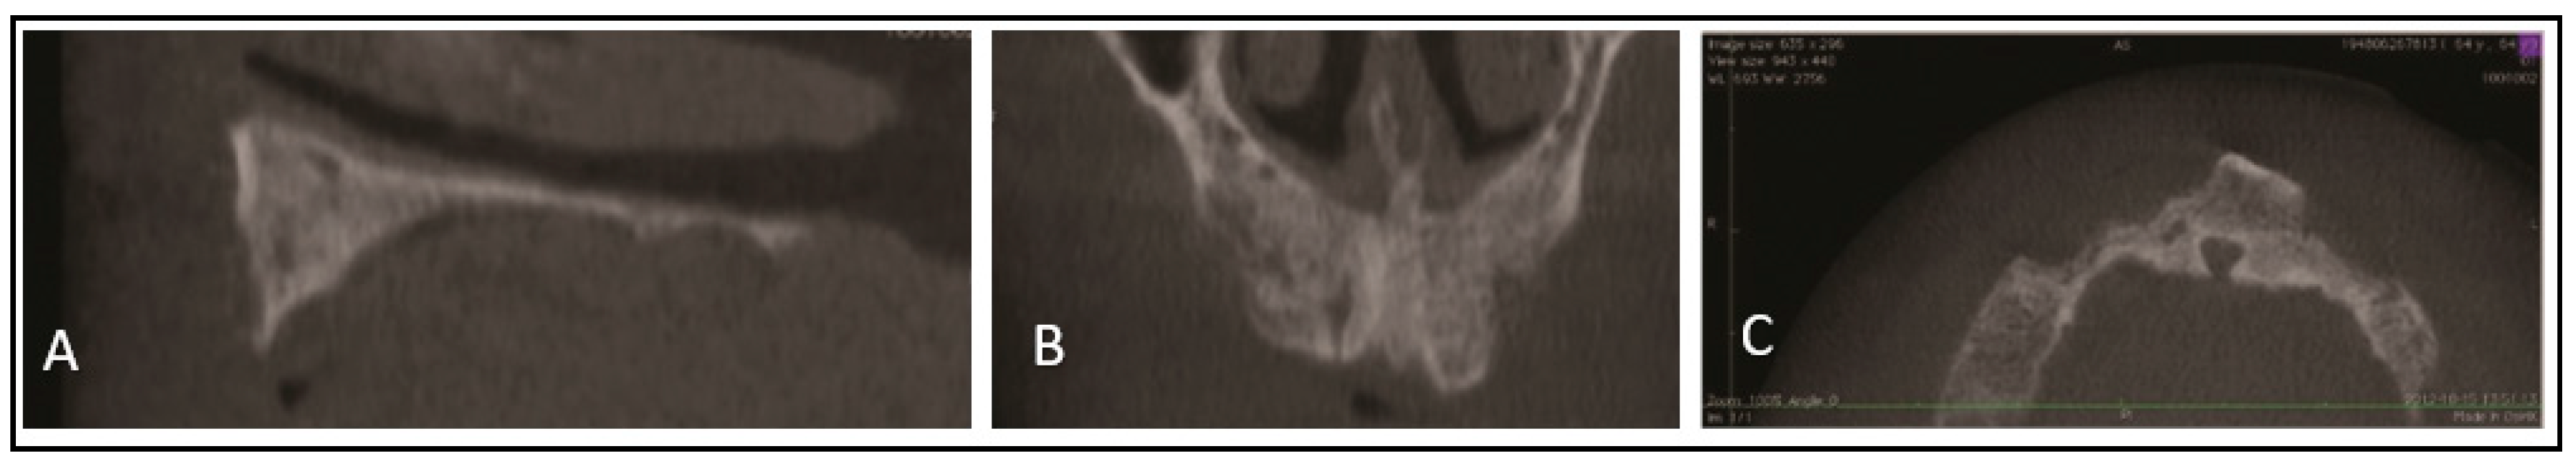

2. Case Report

2.1. Methods

2.2. Surgical Phase